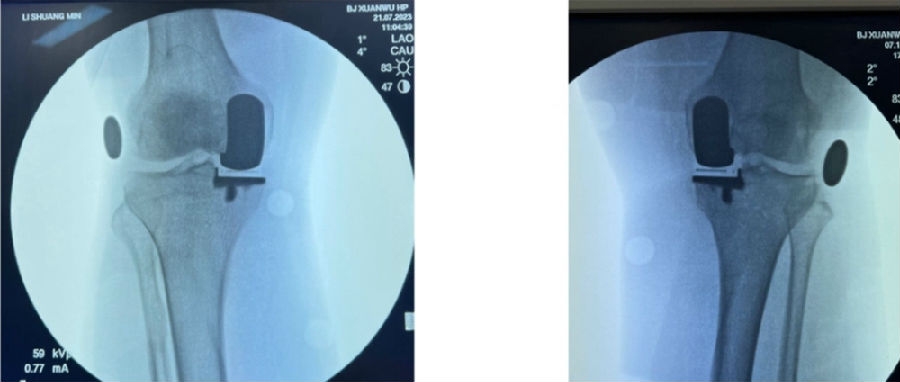

12、术后拍片

目前,笔者团队已经做了70多例,在早期探索过程中可能会出现一些问题,但是之后基本上都是比较好的,术后片子比较赏心悦目。

典型病例

简单总结一下近期的数据,共20例患者的20例膝关节,男5人(25%),女15人(75%),左膝11例(55%),右膝9例(45%)。平均年龄69.8+5.6岁。以±3°作为整个导板设计规划与实际实施的幅度标准。术前规划与术后实际型号没有任何区别,是100%的符合度。

胫骨后倾角有95%的符合度,胫骨内翻角是100%的符合度;胫骨旋转仍然存在一个相对大的差距,但是比传统工具要更好,有70%的病人胫骨内旋角是在范围之内。

股骨在冠状面的角度上也是比较好的表现,股骨内翻角存在95%的符合度,股骨内外旋转角稍差一点,但也达到70%。目前唯一还存在不太满意的地方就是矢状面上股骨假体低头,这个角度偏差度和术前规划差距较大,有50%的准确。